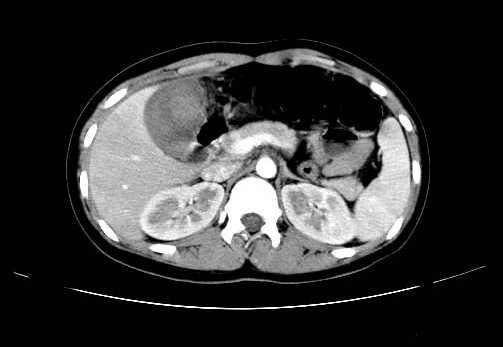

女 16岁  右上腹痛一天,无其他不适

肿块最大径位于十二指肠降段与水平段移行处,并且与肝脏压迹呈“0”形征,可以考虑位于肝外并与胃肠道关系紧密,考虑胃肠道间质瘤(gist)可能较大,须除外神经节起源肿瘤。

肿块与十二指肠关系密切,支持间质瘤诊断.肝脏与结肠均为受压改变.

右下腹巨大肿快,密度不均匀,内见坏死低密度区,边界清楚,与周边胀器明显有分界,未见强化,多考虑来源于间叶组织的良性肿物.

病灶巨大,少部分向肠腔内生长,大部分向长腔外生长。其密度不均匀,增强显示明显不均匀强化,并见有大片状始终不强化的不规则坏死液化区。虽然病灶中上部形态尚可,病人又如此年轻,但中下部形态、密度、强化特点强烈提示为恶性病灶。综上,我考虑本病例为:恶性胃肠道间质瘤。